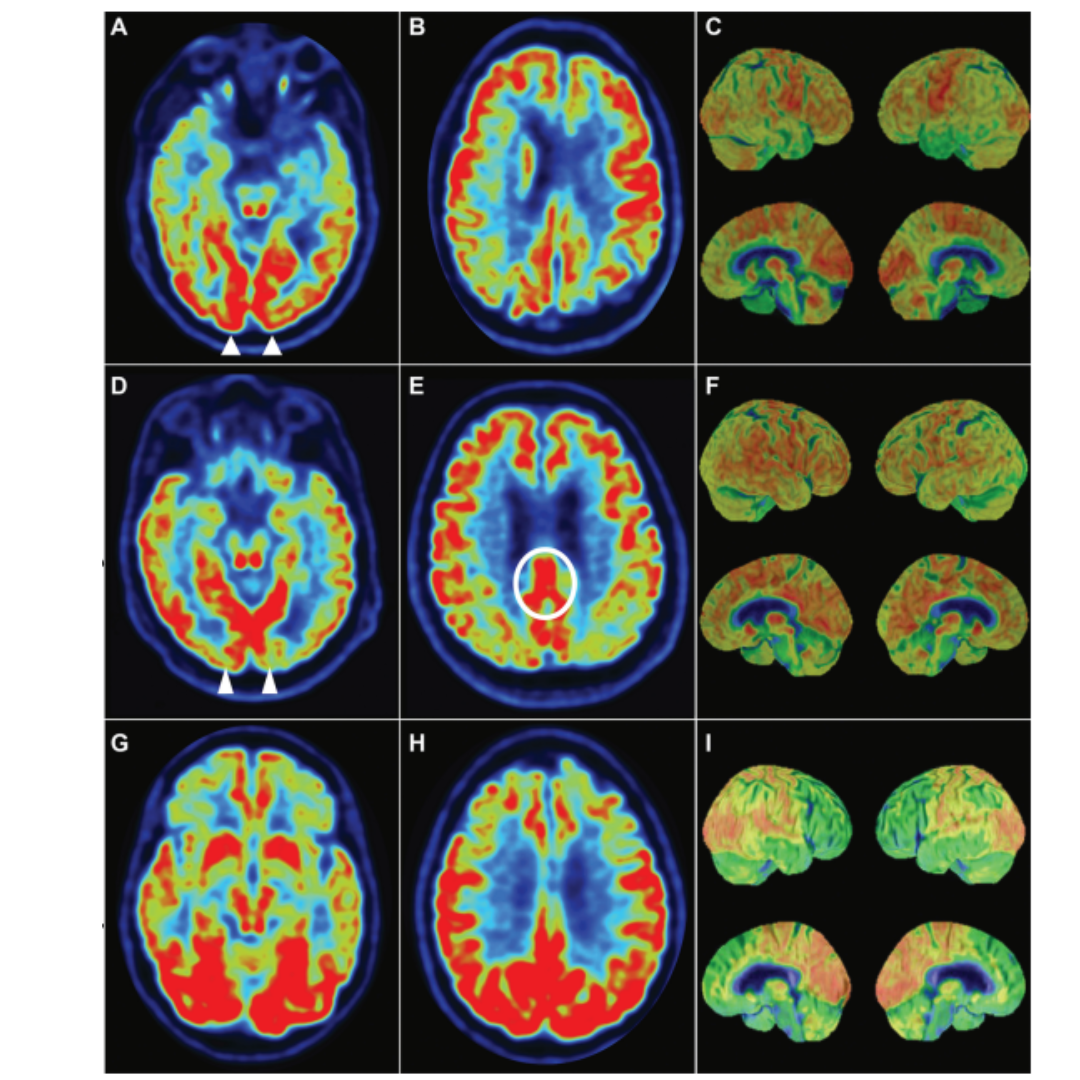

Qual doença eh qual no PET?

A

Numere cada uma das variantes de acordo com PET

Observe a imagem e correlacione a cor com o tipo de APP(agramática, semantica ou logopenica

agramática: vermelho logopenica: roxo semantica: verde